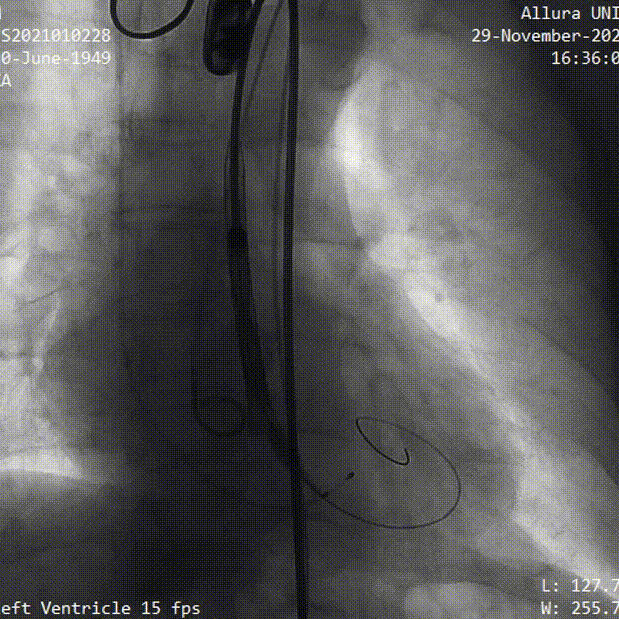

瓣膜释放

球囊后扩

术后造影

术后即刻评估

术后压差从104mmHg降至10mmHg,无瓣周漏,瓣膜正常工作,血流动力学即刻得到改善。术后第13小时,患者下床活动。